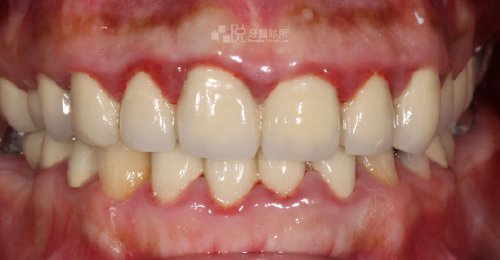

原先有嚴重的牙周病,搭配 4 次的水雷射,約 1 個月的治療時間,就有顯著改善牙周病問題。

舊有假牙侵犯到「生物寬度」(意指假牙邊緣放到牙肉底下太深的位置),導致牙齦有紅腫流血悶痛的發炎反應,本來的牙齒長度偏短、左右牙齦高度不對稱的狀況。

透過【水雷射牙冠增長術】後,讓牙齦恢復健康、和諧的外觀,並完成全口假牙的重建。